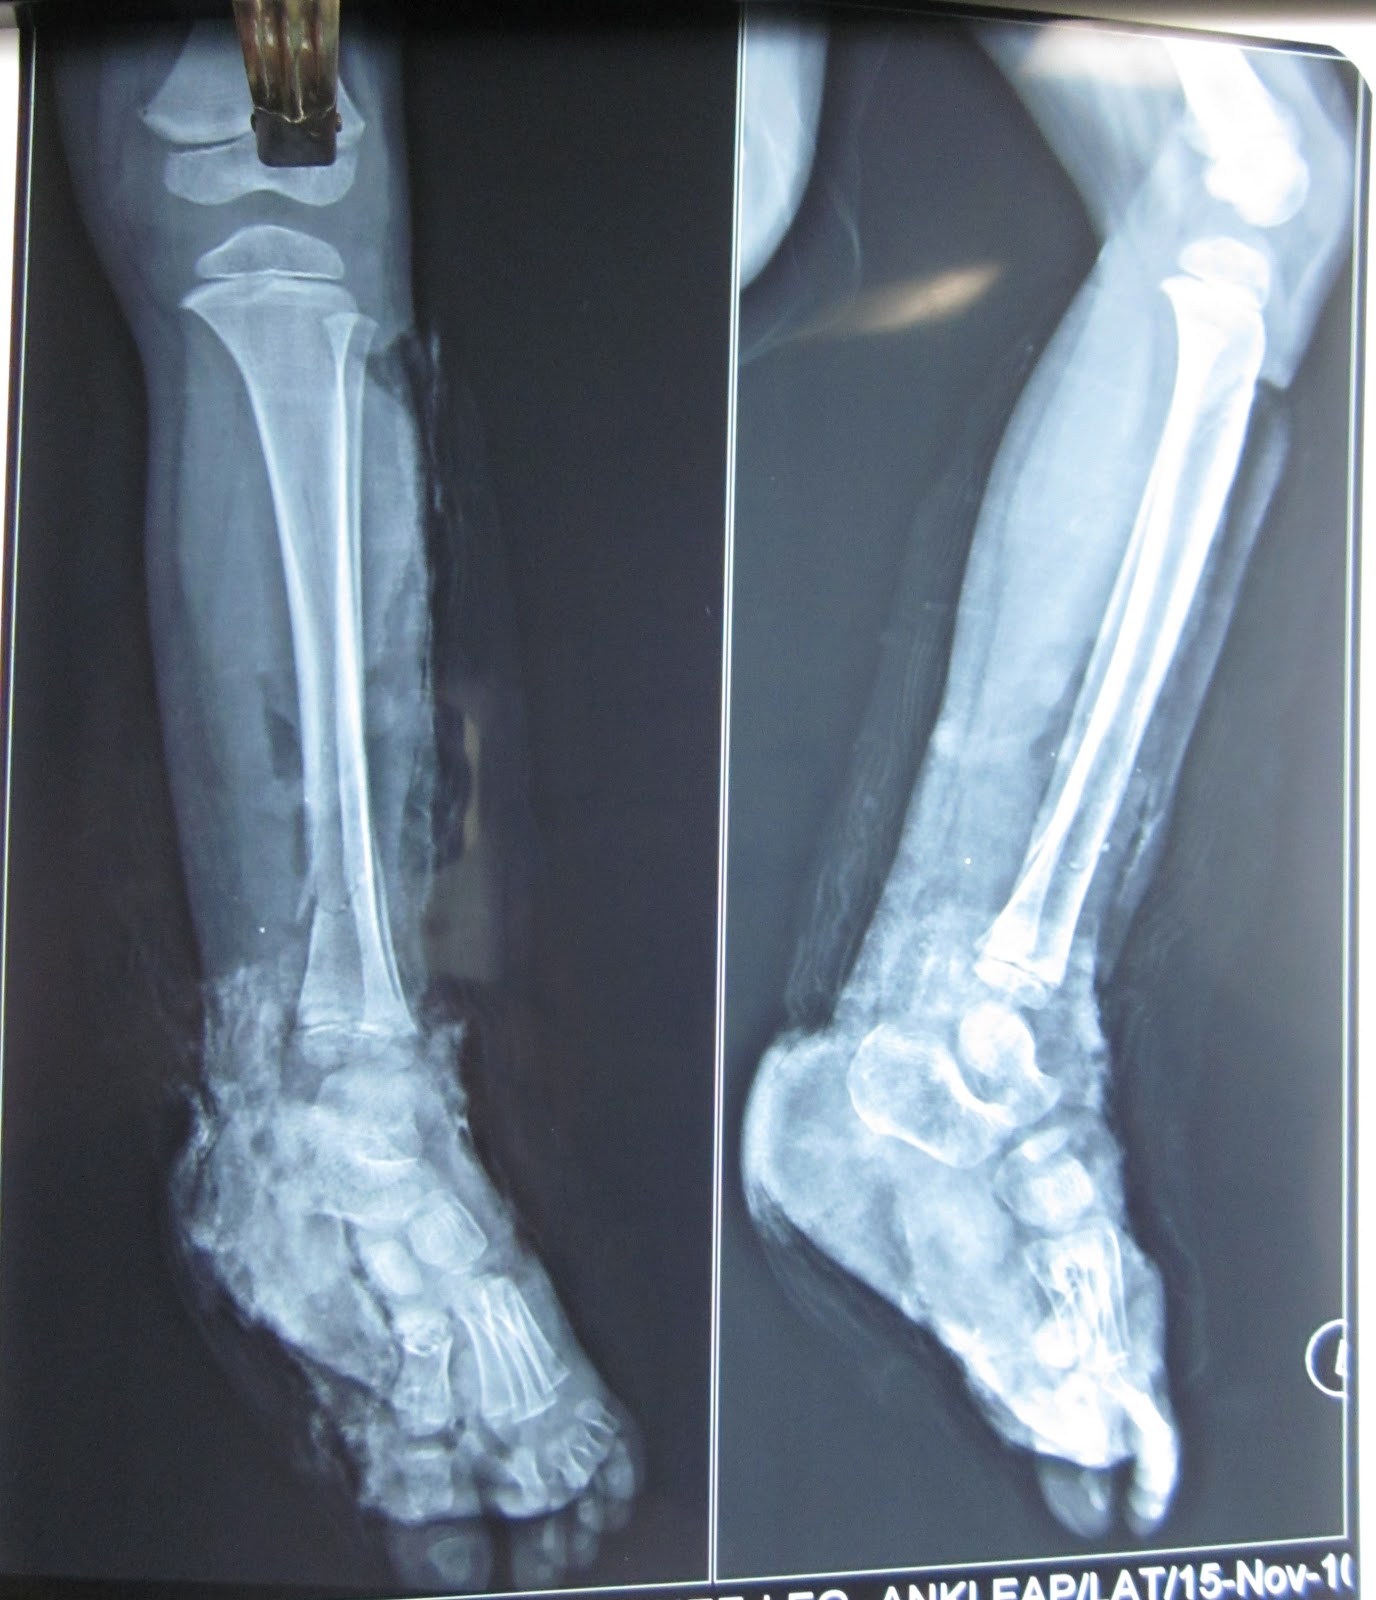

CRUSH INJURY FOOT, LOWER LIMB INJURIES AND LIMB SALVAGE MAJOR CRUSH

TRAUMATIC AMPUTATION OF MIDFOOT CRUSH INJURY FOOT, LOWER LIMB Crush Injury To Lower Leg Compartment syndrome, particularly of the lower limbs, is also a common sequela of crush injury, which may require fasciotomy or. When should you be concerned for crush syndrome? Crush injury is due to direct physical trauma and compression of the human body, most commonly involving the lower extremities. Introduction crush injuries result from physical compression of muscles and may lead. Crush Injury To Lower Leg.

CRUSH INJURY FOOT, LOWER LIMB INJURIES AND LIMB SALVAGE MAJOR CRUSH Crush Injury To Lower Leg Primary amputation may be considered in those with a combination of uncontrollable hemodynamic instability;. Crush injury is due to direct physical trauma and compression of the human body, most commonly involving the lower extremities. Compartment syndrome, particularly of the lower limbs, is also a common sequela of crush injury, which may require fasciotomy or. When should you be concerned for. Crush Injury To Lower Leg.

CRUSH INJURY FOOT OPEN ANKLE JOINT FREE LATISSIMUS DORSI MUSCLE Crush Injury To Lower Leg Severe crush injury results from direct physical trauma to the torso, extremities, or other parts of the body from an external. Primary amputation may be considered in those with a combination of uncontrollable hemodynamic instability;. When should you be concerned for crush syndrome? Compartment syndrome, particularly of the lower limbs, is also a common sequela of crush injury, which may. Crush Injury To Lower Leg.

CRUSH INJURY FOOT, LOWER LIMB INJURIES AND LIMB SALVAGE MAJOR Crush Injury To Lower Leg Primary amputation may be considered in those with a combination of uncontrollable hemodynamic instability;. This type of injury most often happens when part of the body is squeezed. Compartment syndrome, particularly of the lower limbs, is also a common sequela of crush injury, which may require fasciotomy or. Severe crush injury results from direct physical trauma to the torso, extremities,. Crush Injury To Lower Leg.